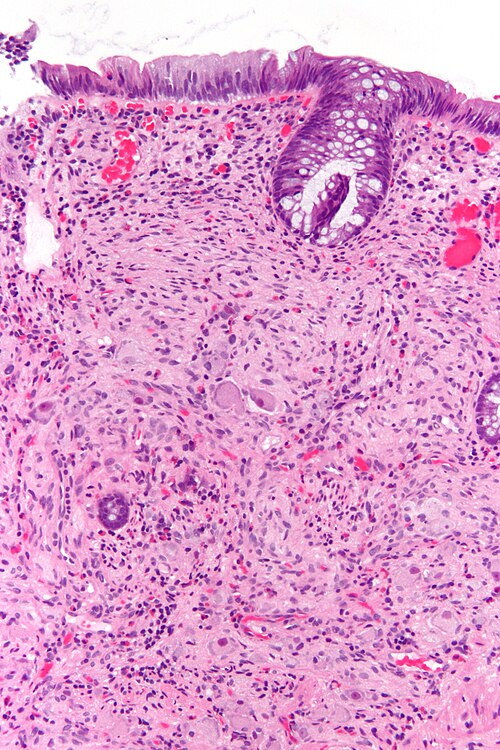

52 year old man, polyp.

Colon.

Intermediate magnification. H&E stain.

There are large cells in the stroma. The cells have a prominent nucleolus!

NSE Large round cells POSITIVE

S-100Spindle cells POSITIVE

Synaptophysin Large round cells POSITIVE

Ganglioneuroma.